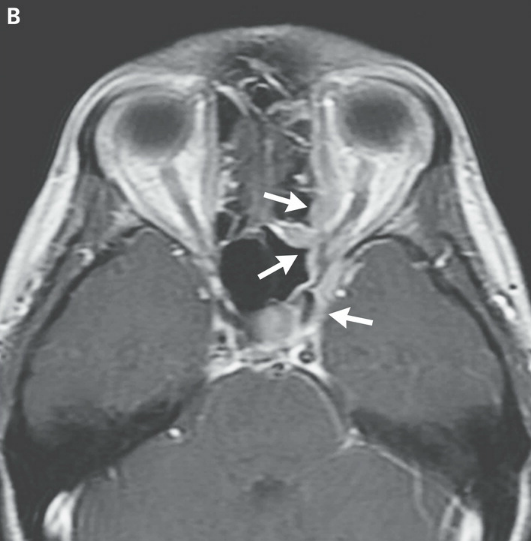

En el examen, la temperatura era de 37,4 ° C; los otros signos vitales y la saturación de oxígeno eran normales. El examen oftalmológico reveló una agudeza visual de 20/20 en el ojo derecho y 20/400 en el ojo izquierdo. Las pupilas eran iguales, redondas y reactivas, con un defecto pupilar aferente izquierdo. Resultados de las pruebas de color visión con placas de color de Ishihara fueron normales en el lado derecho (8/8 correctamente identificados) y 0/8 de la izquierda. La presión intraocular era 13 mm Hg en el lado derecho y 11 mm Hg a la izquierda. Examen con lámpara de hendidura reveló segmentos normales anteriores bilateralmente. El examen de la motilidad extraocular reveló plena movilidad en el ojo derecho; el ojo izquierdo tenía aducción limitada, supraducción y infraducción, con intorsion mínimo en intento de secuestro (Figura 2 ).

Figura 2

Fotografías de los ojos del paciente.

En la mirada primaria (Panel C) hay leve ptosis del párpado superior izquierdo.El ojo izquierdo tiene leve déficit de elevación (Panel A), aducción (Panel B), y depresión (Panel E), y no tiene abeducción (PanelD).